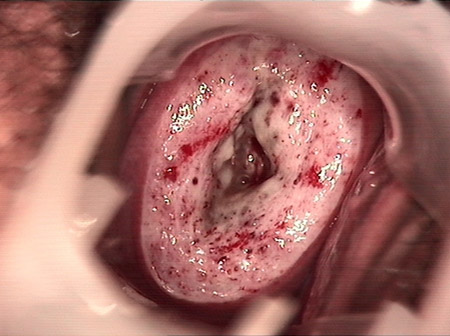

• CIN 2-3 leep術后CIN 2-3 leep術后